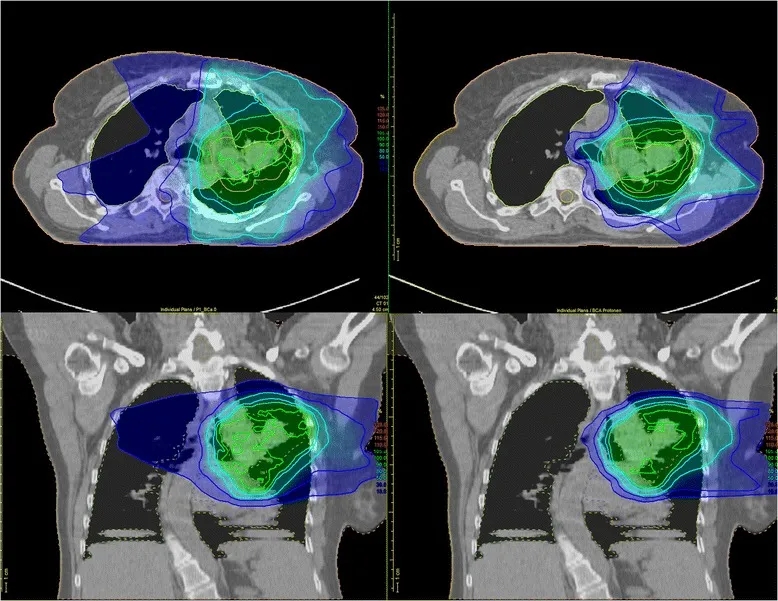

▲图源“Int J Radiat Oncol Biol Phys”,版权归原作者所有,如无意中侵犯了知识产权,请联系我们删除

安全性数据表现优异:47例患者(92%)仅出现1级及以下急性肺毒性,仅3例为2级、1例为3级,无4级及以上急性肺毒性发生,且患者远期毒性反应极少。此外,既往研究针对局部晚期NSCLC患者的剂量分布分析也证实了质子治疗的安全性优势——与调强光子放疗(IMRT)相比,质子治疗对危及器官(OAR)的剂量显著更低:传统IMRT易使辐射波及肿瘤周围健康组织(详见下图左),而质子疗法可将大部分辐射精准集中于肿瘤靶区(详见下图右)。